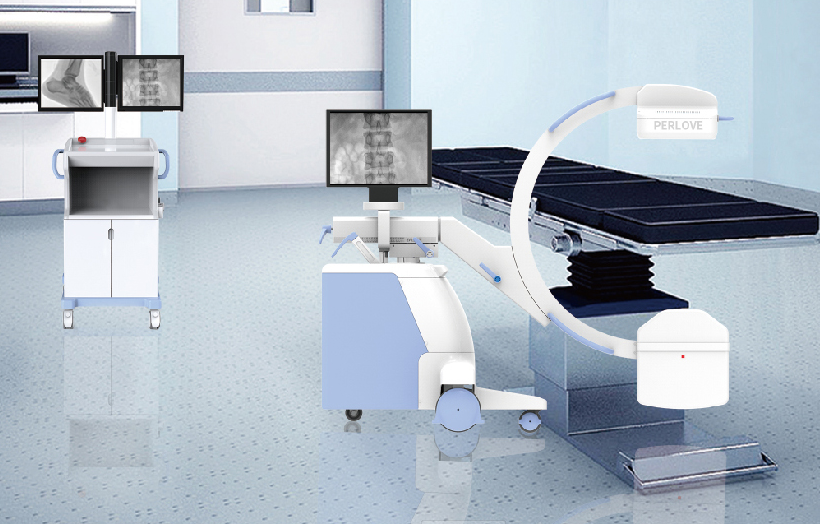

临床适用科室:骨科、普通外科、矫形外科、创伤外科、泌尿外科、脊柱外科、疼痛外科、消化科、妇科等科室。

图形化操控界面设计:设有多种人体特征摄影参数,操作简便。双向红光十字定位系统:实现无射线下的高效定位。信息共享:遵循DICOM3.0格式接口,可无缝对接云PACS系统。

多角度自由旋转,满足患者复杂摆位需求。